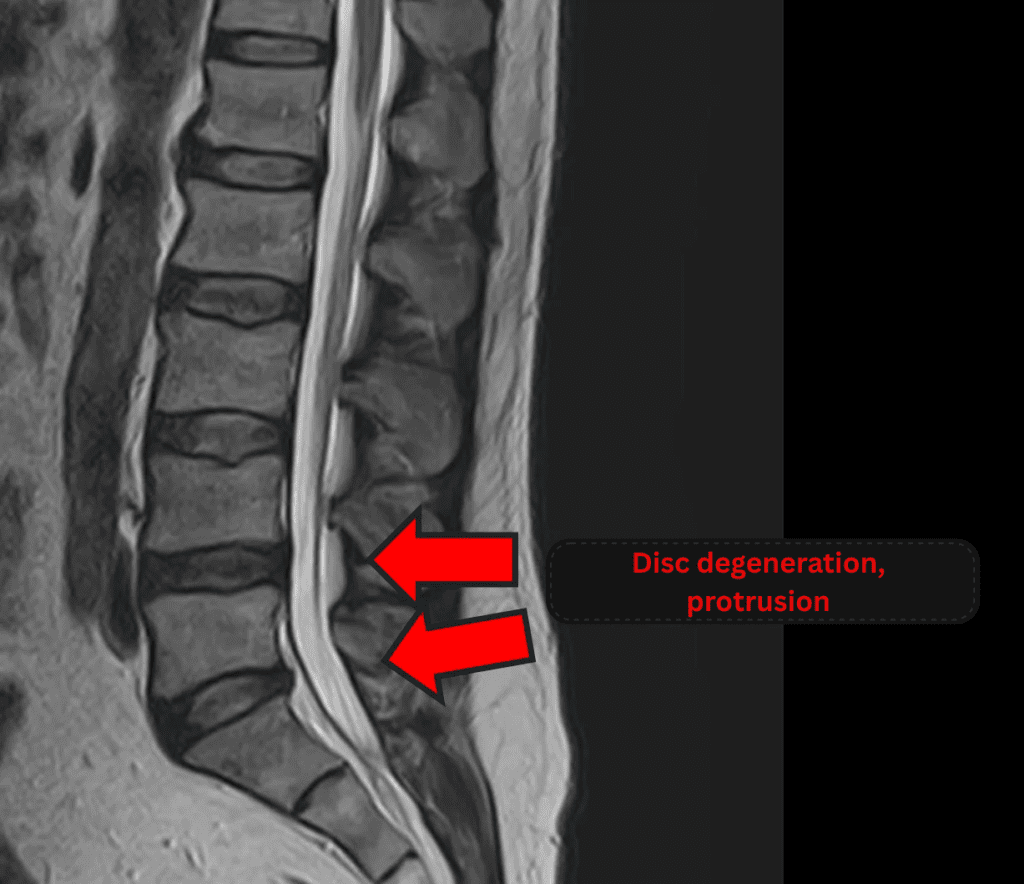

Imaging and findings

- L4/5, L5/S: Disc degeneration, bulging, and foraminal stenosis

The above findings were also observed on the imaging.

Compression of the spinal canal due to disc pathology at L4/5 and L5/S is considered the most likely cause of the patient’s symptoms.